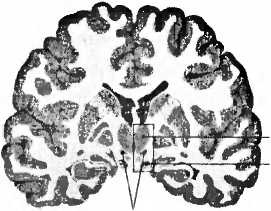

субталамическое ядро

Рис. 22. Пациенту с болезнью Паркинсона имплантирован электрод (Е) в нужное место в субталамическом ядре (nucleus subthalamicus). Т — таламус; ТО — tractus opticus (зрительный тракт).

В настоящее время в мире примерно 35 000 человек живут с имплантированным в мозг электродом. Как во всякой действенной терапии, здесь тоже возможны побочные действия. В процессе социальных контактов с партнером или среди рабочего окружения люди с болезнью Паркинсона, которым имплантирован электрод, могут сталкиваться с затруднениями. Хотя большинство пациентов были очень довольны качеством своей жизни, их семьи сообщали, что иногда они делались более возбудимыми и эмоционально неустойчивыми. У 9 % были отмечены психические осложнения: повышенная импульсивность при принятии решений или приступы плача. Стимуляция электродом может усиливать депрессию, а иногда даже приводить к самоубийству. Нам известны пациенты, у которых электроды находились в нужном месте субталамического ядра (рис. 22) и которые пытались совершить самоубийство. Десять лет тому назад неврология еще не проявляла интереса к этой взаимосвязи. Бывает, что имплантация электрода приводит к кровотечению или повреждению мозга, после чего отмечаются проявления деменции, которые исчезают, если стимулятор по-другому отрегулировать. Есть также сведения о возникновении психозов, сексуальной несдержанности и игрозависимости. Пациент, который до операции был типичным бережливым голландцем, после имплантации электрода уже больше не мог спокойно пройти мимо игрового автомата. Лишь после того, как через несколько лет он из-за громадных долгов вынужден был продать дом, его подруга хотела его оставить и он совершил попытку самоубийства, решено было обратиться к врачу. Игрозависимость может возникнуть также при классическом лечении болезни Паркинсона леводопой. Дофаминовая система (рис. 15) играет центральную роль при возникновении зависимостей. Необычное побочное действие наблюдалось у пациента, который стал покупать дома в Испании и Турции, не имея для этого средств; несмотря ни на что, он отказывался отключить стимулятор. Стимуляция глубинными электродами может иногда вызывать нарушения мышления, речи и памяти. Побочные явления психического характера, вызванные глубокой электростимуляцией электродами, всё же в основном преходящи, они хорошо поддаются лечению и их даже возможно предотвращать. Они также дают нам возможность что-то узнать о функции структур и нейронных цепей мозга при симптомах психических заболеваний, как, например, о роли дофаминовой системы при формировании зависимостей. Успех воздействия глубинных электродов при лечении болезни Паркинсона привел к тому, что сейчас их применяют при многих неврологических и психических картинах болезни: невыносимых болях, кластерных головных болях, депрессиях, страхах, мышечных спазмах, самокалечении и обсессивно-компульсивных расстройствах. В ходу исследования лечения ожирения и зависимостей с помощью глубинной имплантации электродов. Возможности приложения этого метода кажутся неисчерпаемыми. Купер о таком и не помышлял, когда в 1952 году по оплошности вызвал кровотечение мозгового сосуда.